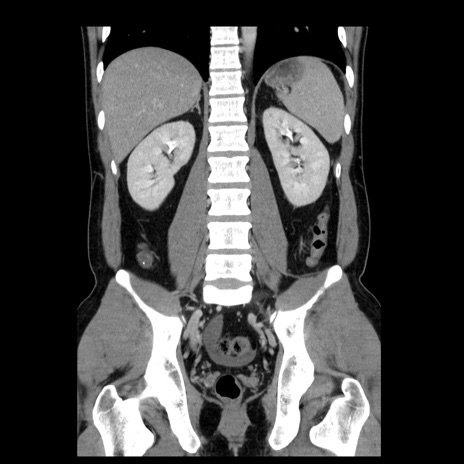

症例4(冠状断像)

【症例】30歳代男性

【主訴】腹痛、嘔吐

【現病歴】昨晩から突然の腹痛あり、その後嘔吐、軟便も出現。腹痛が改善しないため救急搬送となる。2日前にしめ鯖の食事歴あり。

【身体所見】意識清明、苦悶様、BP 135/90mmHg、BT 35.7℃、腹部:平坦、やや硬、心窩部〜臍部に自発痛、圧痛あり、筋性防御+、反跳痛-

【データ】WBC 8100、CRP 0.57